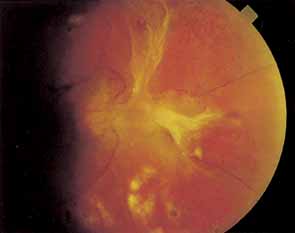

Fig. 3 A. Diabetic retinopathy with multiple microaneurysms, dot hemorrhages, and early neovascularization of the optic disc (NVD). A small blot hemorrhage is seen inferiorly. B. Continued. Midphase of the fluorescein angiogram. Patent microaneurysms are seen as hyperfluorescent dots. Note that most microaneurysms cannot be seen ophthalmoscopically. There is some enlargement of the foveal avascular zone because of some occluded capillaries. Temporally there is a larger zone of capillary nonperfusion. The NVD is beginning to leak. C. Late phase of the fluorescein angiogram showing diffuse leakage of fluorescein into the macula.

It is often difficult to distinguish a small dot hemorrhage from a microaneurysm by ophthalmoscopy alone. On fluorescein angiography patent microaneurysms will fill with dye quickly and then leak,5 unlike a small dot hemorrhage that will block fluorescence (see Fig. 3). However, angiography cannot distinguish a hemorrhage from a microaneurysm filled with clotted blood. Because fluorescein passes easily though them, we usually see many more microaneurysms on fluorescein angiography than are apparent on examination.6

When the wall of a capillary or microaneurysm is thin, it may rupture, giving rise to an intraretinal hemorrhage. If the hemorrhage is deep (i.e., in the inner nuclear layer or outer plexiform layer), it usually has a round or oval shape (“dot or blot”) (see Fig. 3). Superficial (nerve fiber layer) hemorrhages, on the other hand, become flame- or splinter-shaped indistinguishable from that seen in hypertensive retinopathy. Although people with diabetes with normal blood pressure may have multiple splinter hemorrhages, they should nevertheless have their blood pressure checked because a frequent complication of diabetes is systemic hypertension.